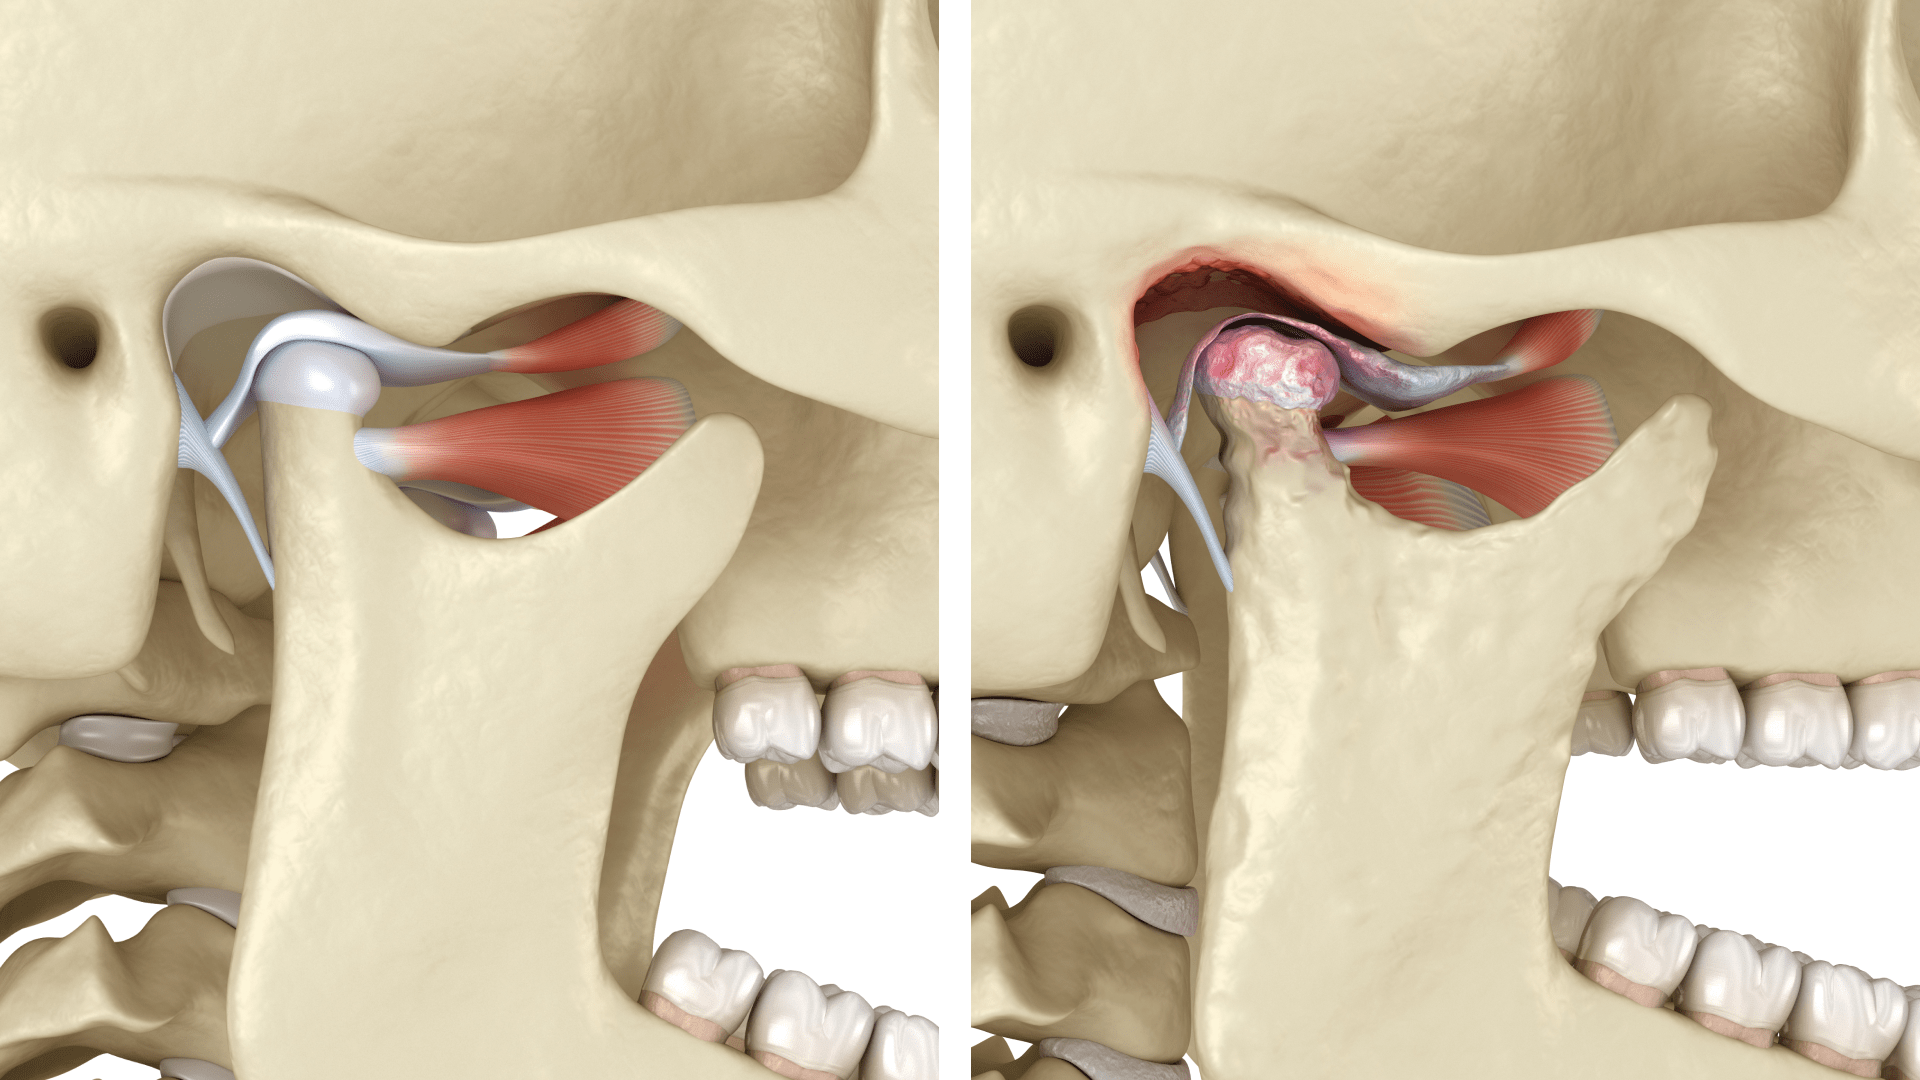

Причини дисфункції суглоба

Дисфункція скронево-нижньощелепного суглоба — це стан, за якого порушується його нормальна робота та координація. У результаті виникають різного ступеня болючі відчуття, а також утруднення, клацання чи хрускіт під час відкривання рота.

Проблеми зі СНЩС досить поширені. За даними Всесвітньої організації охорони здоров’я, на них страждає близько третини населення, хоча реальна кількість випадків значно вища. Експерти вважають, що понад 60 % людей мають ті чи інші прояви дисфункції, але просто не звертають на них уваги.

Причини розвитку дисфункції можуть бути різними. Найчастіше вона пов’язана з неправильним прикусом, через який змінюється траєкторія руху нижньої щелепи та збільшується навантаження на суглоб. Подібний ефект спостерігається і при бруксизмі.

Сильні емоційні навантаження, постійна напруга м’язів обличчя або навіть шкідливі звички також можуть спричинити дисбаланс у роботі суглоба. У деяких випадках дисфункція розвивається після травм щелепи або лицьових кісток, що порушують анатомічну цілісність СНЩС.

Не варто виключати й системні чинники. Ендокринні порушення, інфекції або обмінні розлади здатні негативно впливати на тканини суглоба, провокуючи запальні процеси. Навіть надмірні фізичні навантаження чи звичка стискати щелепи під час стресу можуть стати причиною розвитку дисфункції СНЩС.